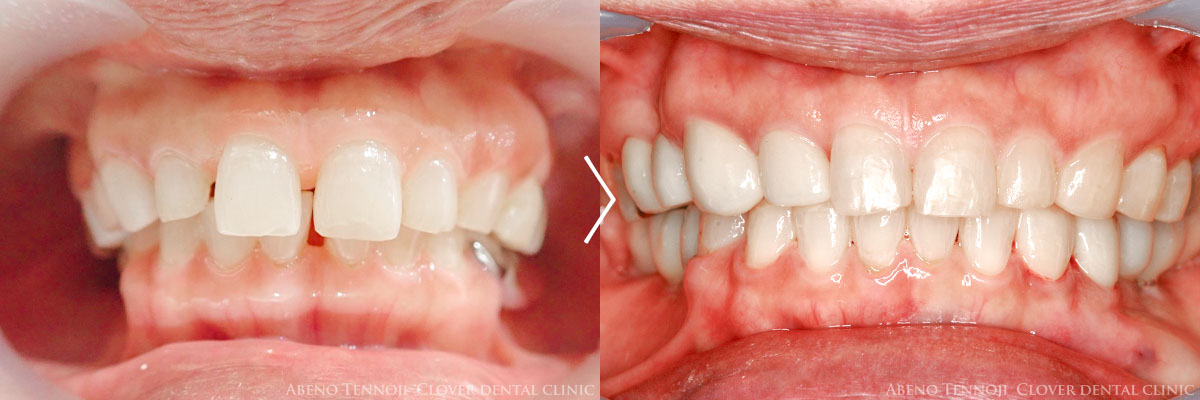

当法人では、インビザラインの多くの実績があります。その実績から、マウスピース矯正のクオリティには自信を持っております。

実はマウスピース矯正にも、様々なレベルがあります。同じインビザラインでもそうです。

実績に裏打ちされた、確実な技術をお約束します。安心の中でのインビザラインを、ぜひおすすめ致します。